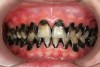

There are several advantages of using SDF in dental treatment. First, it showed an antimicrobial activity against mono-species, dual-species, and multi-species cariogenic biofilm.14-16 Silver ions are bactericidal metal cations that inhibit biofilm formation.17 Studies have indicated that silver interacts with sulfhydryl groups of proteins and DNA, thus altering hydrogen bonding and inhibiting respiratory processes, DNA unwinding, cell-wall synthesis, and cell division.18 At the macro level, these interactions affect bacterial killing and inhibit biofilm formation.17 Second, fluoride promotes caries lesion remineralization. Fluoride has been indicated to react with hydroxyapatite and generate calcium fluoride, which is a reservoir of fluoride, and facilitate further remineralization.19 An ex vivo study reported surface microhardness of the surface layer of the arrested caries after SDF applications was comparable with the unaffected sound dentin20 (Figure 1 and Figure 2). This is consistent with another study, in which a high remineralized zone was observed on the surface of arrested caries from exfoliated teeth with SDF treatment21 (Figure 3 and Figure 4). Third, its application procedures are simple and do not require injection or drilling, and the treatment does not involve expensive support infrastructure equipment such as piped water and electricity. The simplicity of the treatment is conducive to treating caries in apprehensive young children who may have intense dental fear, uncooperative patients with special needs, or elderly patients who have difficulty adapting to traditional dental care. It also allows trained workers to deliver the treatment to people who live in the area but who may not be able to easily access dental service.22 Patient compliance and satisfaction is often good when the patient is provided a clear explanation of the treatment outcome.23,24 Finally, the cost of SDF treatment is low and should be affordable in most communities.

Fig 1. Ground section of a primary incisor with arrested caries lesion after SDF treatment: arrested caries that had SDF treatment. (image from Chu and Lo, 2008, ref 20 [reprinted with approval])

Figure 1